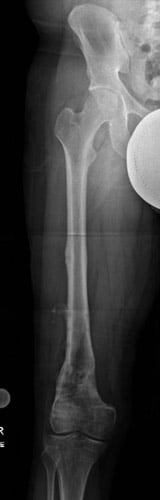

Case #74: Femur lengthening and deformity correction.